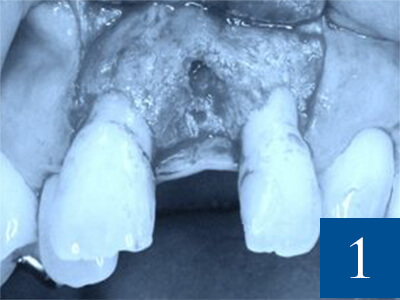

骨造成術は、失った骨を再生・補填し、

インプラント治療を可能にする技術です。

歯がなくなってから長時間が経過すると、あごの骨は衰えてしまい、

インプラントを支える骨がなくなってインプラント治療が難しくなる場合があります。

しかし、骨造成術をすることでインプラント治療に必要な骨のボリュームが得られ、

インプラント治療が可能になります。

骨造成術は、インプラントの安定性と

成功率を向上させるメリットがあります。